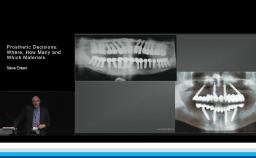

Graduated from Ohio State University College of Dentistry, after which he completed a General Practice Residency at Mount Sinai Medical Center of Chicago. He is certified in prosthodontics and has a MSc from the Mayo Graduate School of Medicine. Dr. Eckert is a diplomat of the American Board of Prosthodontics and a Fellow of the American College of Prosthodontists, Academy of Prosthodontics, Academy of Osseointegration, American Academy of Maxillofacial Prosthetics and the ITI. He is past president of the AO, AAMP and the AP and a Director and Examiner for the American Board of Prosthodontics, where he is currently Vice President. He is also the Editor-in-Chief of the IJOMI.